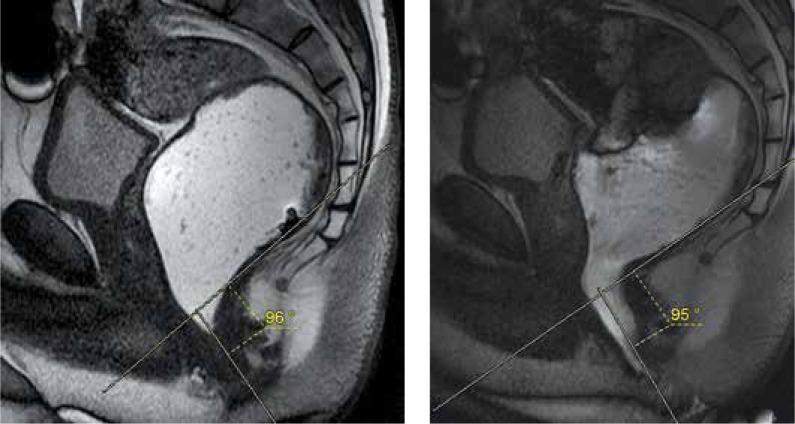

Magnetic resonance defecography findings of dyssynergic defecation.

Dyssynergic defecation (DD) is defined as paradoxical contraction or inadequate relaxation of the pelvic floor muscles during defecation, which causes functional constipation. Along with the anal manometry and balloon expulsion tests, magnetic resonance (MR) defecography is widely used to diagnose or rule out pelvic dyssynergia. Besides the functional abnormality, structural pathologies like rectocele, rectal intussusception, or rectal prolapse accompanying DD can also be well demonstrated by MR defecography. This examination can be an uncomfortable experience for the patient, so the imaging method and the importance of patient cooperation must be explained in detail. The defecatory phase of the examination is indispensable for evaluation, and inadequate effort should be ruled out before diagnosing DD. MR defecography provides important data for the diagnosis of DD, but optimal imaging criteria should be applied. Further tests can be suggested if patient co-operation is not sufficient or MR defecography findings are irrelevant.

排便协同失调(DD)被定义为排便时盆底肌肉反常收缩或松弛不足,从而导致功能性便秘。除肛门测压法和气囊排出试验外,磁共振(MR)排粪造影术也被广泛用于诊断或排除盆腔协同失调。除了功能异常外,MR排粪造影术还能很好地显示伴随DD出现的诸如直肠膨出、直肠套叠或直肠脱垂等结构病变。这项检查对患者来说可能是一次不舒服的体验,因此必须详细解释成像方法以及患者配合的重要性。检查的排便阶段对于评估不可或缺,在诊断DD之前应排除用力不足的情况。MR排粪造影术为DD的诊断提供了重要数据,但应采用最佳成像标准。如果患者配合不充分或MR排粪造影结果不相关,则可建议进一步检查。